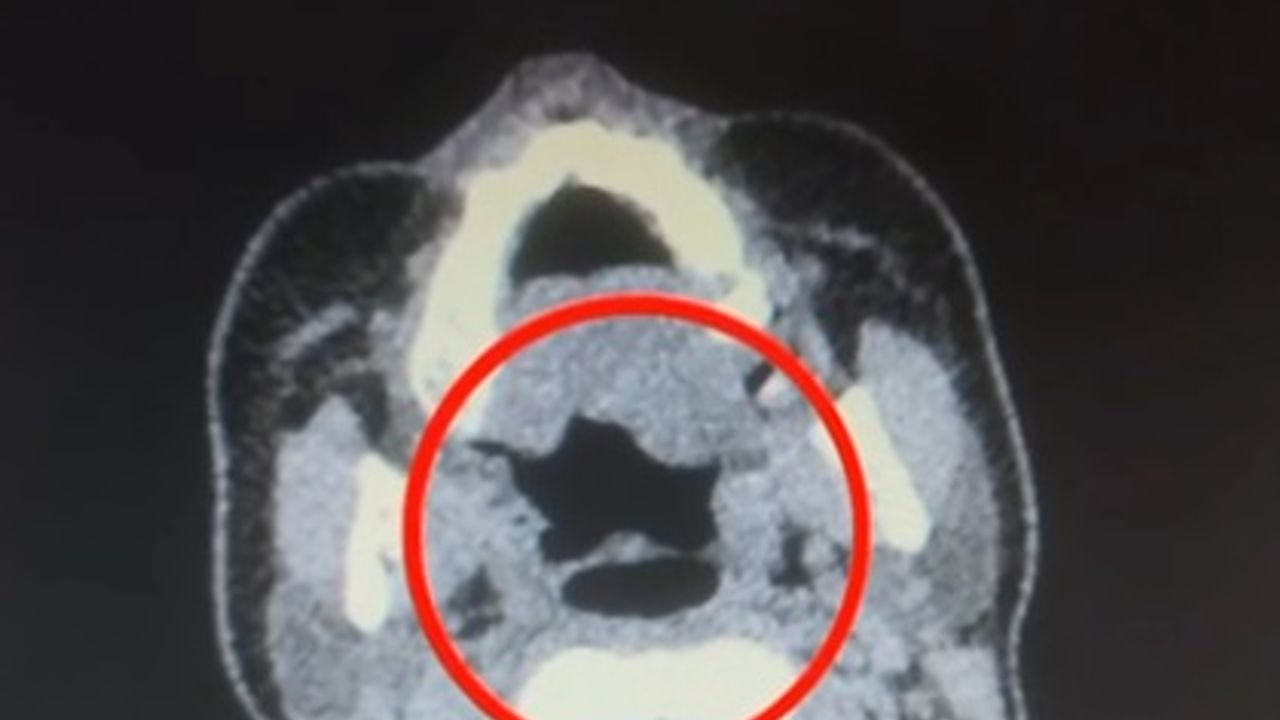

İl Emniyet Müdürlüğü Narkotik Suçlarla Mücadele Şube Müdürlüğü ekipleri, ‘Uluslararası uyuşturucu madde ticareti’ yapan kuryelerin yakalanması için çalışma başlattı. Bu kapsamda gerçekleştirilen operasyonda A.R. isimli kadın yakalandı. Gözaltına alınan şüpheli muayene için Kayseri Şehir Hastanesi'ne götürüldü. Röntgen ve ultrasonda, A.R.’nin midesinde uyuşturucu madde olduğu saptandı. Şüphelinin midesinden kapsül halinde 500 gram metamfetamin, sağlık ekibinin müdahalesiyle beraber çıkarıldı. Taburcu edilen A.R., polis merkezine götürüldü.